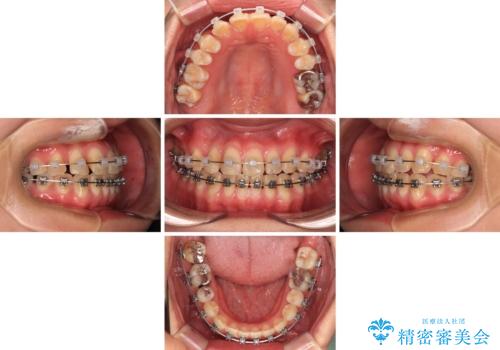

- 矯正装置

- メタルブラケット

舌の突出癖により、治療過程でスペースが多くできましたが、舌のトレーニングを頑張っていただき、1年強で終えることができました。